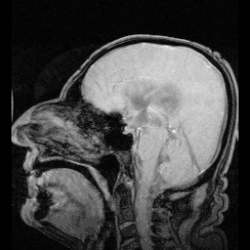

![]() The cerebrospinal fluid circulates in the subarachnoid space around the brain and spinal cord, and in the ventricles of the brain. | |

![]() Image showing the location of CSF highlighting the brain's ventricular system | |